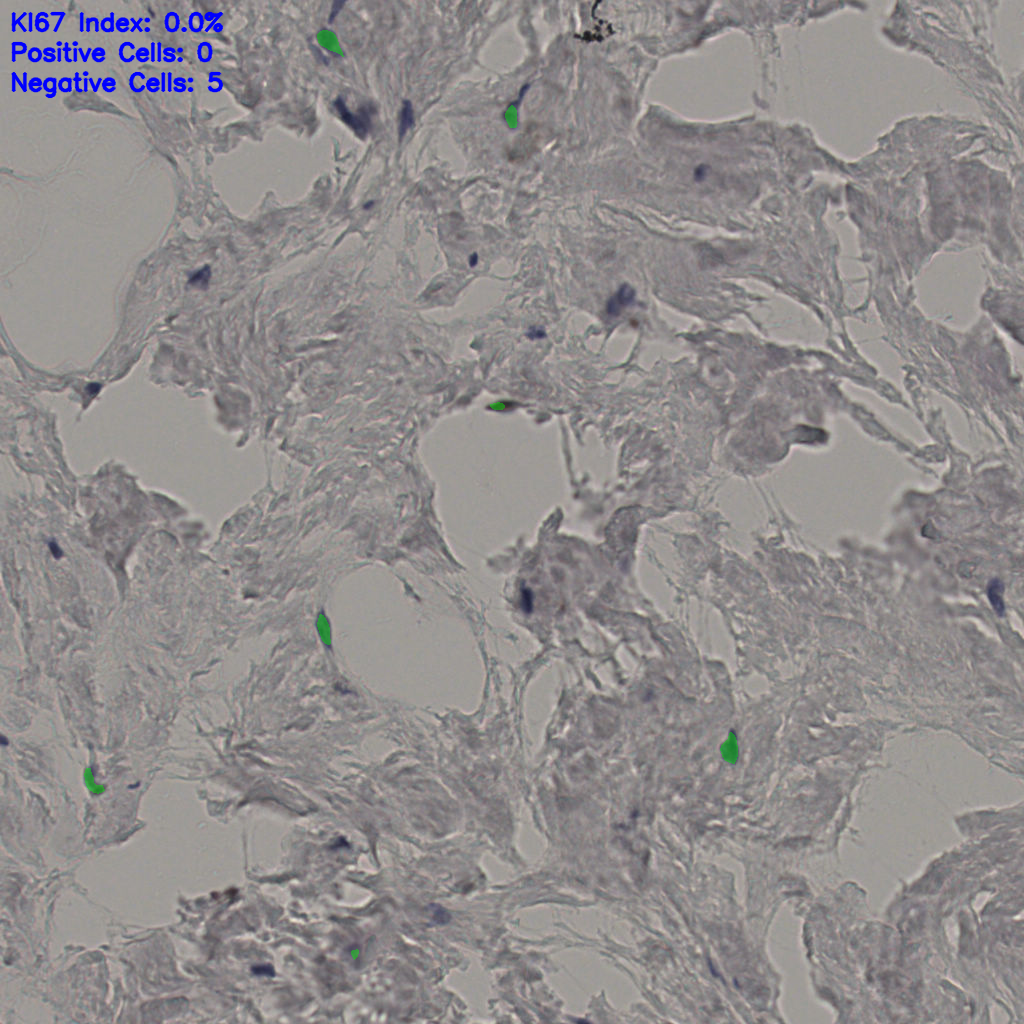

5.31%

Ki67 指数

阴 19502 阳 1093

总切片 2970

有效 554

已标记 554

有效率 19%